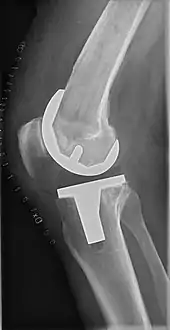

The surgery involves exposure of the front of the knee, with detachment of part of the quadriceps muscle (vastus medialis) from the patella. The patella is displaced to one side of the joint, allowing exposure of the distal end of the femur and the proximal end of the tibia. The ends of these bones then are cut accurately to shape, using cutting guides oriented to the long axis of the bones. The cartilages and the anterior cruciate ligament are removed; the posterior cruciate ligament also may be removed but the tibial and fibular collateral ligaments are preserved.[20] Whether the posterior cruciate ligament is removed or preserved depends on the type of implant used, although there appears to be no clear difference in knee function or range of motion favoring either approach.[20] Metal components are then impacted onto the bone or fixed using polymethylmethacrylate (PMMA) cement. Alternative techniques exist that affix the implant without cement. These cement-less techniques may involve osseointegration, including porous metal prostheses. Finally, stability and range of motion are checked, followed by irrigation, hemostasis, placement of hemovacs, and closure.[21]

Femoral replacement

A round-ended implant is used for the femur, mimicking the natural shape of the joint. On the tibia the component is flat, although it sometimes has a stem that goes down inside the bone for further stability. A flattened or slightly dished high-density polyethylene surface is then inserted onto the tibial component so the weight is transferred metal to plastic, not metal to metal. During the operation any deformities must be corrected, and the ligaments balanced so the knee has a good range of movement, and is stable and aligned. In some cases the articular surface of the patella also is removed and replaced by a polyethylene button cemented to the posterior surface of the patella. In other cases, the patella is replaced unaltered.